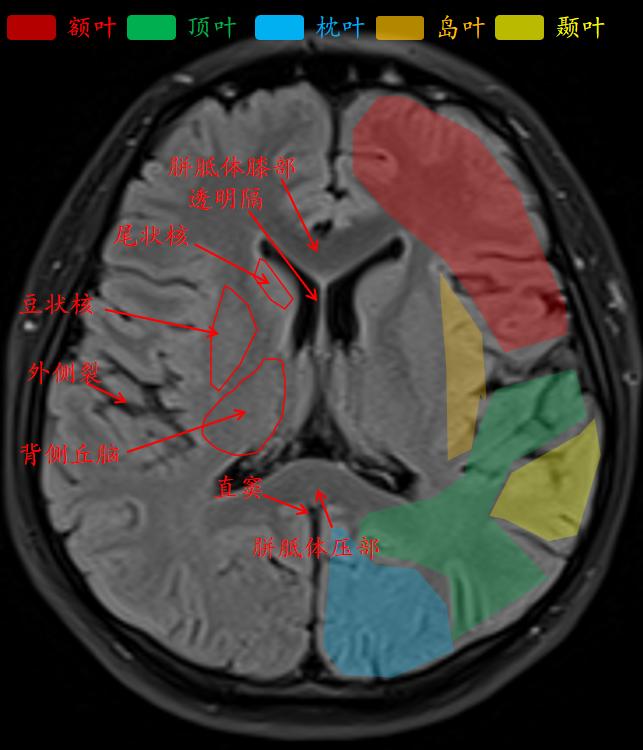

外侧沟把额叶、颞叶和顶叶分开。

白质是传入或传出大脑皮质的神经纤维组成。

灰质里的基底核是基底神经节。